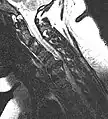

• Magnetic resonance imaging is the gold standard study for confirming a suspected LDH. With a diagnostic accuracy of 97%, it is the most sensitive study to visualize a herniated disc due to its significant ability in soft tissue visualization. MRI also has higher inter-observer reliability than other imaging modalities. It suggests disc herniation when it shows an increased T2-weighted signal at the posterior 10% of the disc. Degenerative disc diseases have shown a correlation with Modic type 1 changes. When evaluating for postoperative lumbar radiculopathies, the recommendation is that the MRI is performed with contrast unless otherwise contraindicated. MRI is more effective than CT in distinguishing inflammatory, malignant, or inflammatory etiologies of LDH. It is indicated relatively early in the course of evaluation (<8 weeks) when the patient presents with relative indications like significant pain, neurological motor deficits, and cauda equina syndrome. Diffusion tensor imaging is a type of MRI sequence used for detecting microstructural changes in the nerve root. It may be beneficial in understanding the changes that occur after herniated lumbar disc compresses a nerve root, and might help in differentiating the patients that need surgical intervention. In patients with a high suspicion of radiculopathy due to lumbar disc herniation, yet the MRI is equivocal or negative, nerve conduction studies are indicated.[44] T2-weighted images allow for clear visualization of protruded disc material in the spinal canal.